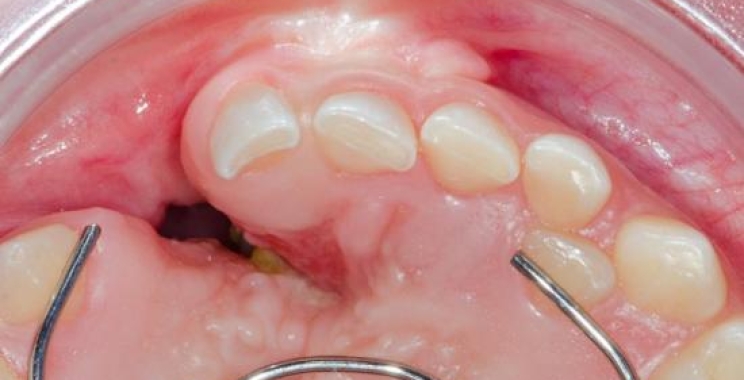

وضع العظم الجديد:

يقوم الطبيب بوضع العظم الجديد بالمكان المطلوب لتعويض المفقود، وفي بعض الحالات يتم تثبيته باستعمال مسامير أو غشاء لضمان استقراره.

تغطية العظم:

بعد ذلك يتم تغطية القسم الجديد باستعمال غشاء حيوي لتعزيز عملية الشفاء، ثم إغلاق اللثة بالخيوط الجراحية لضمان التئام المنطقة بشكل تام.